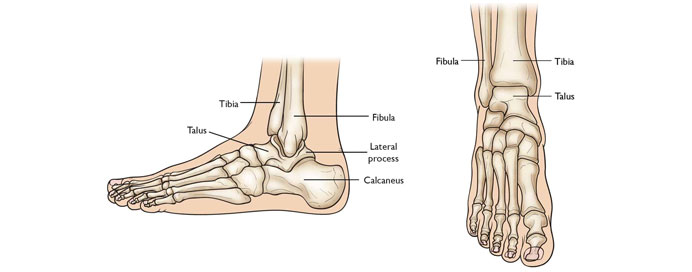

Foot & Ankle Joint

The foot and ankle joint work together to provide stability, movement, and weight-bearing support for the body. The ankle joint is a hinge joint, formed by the tibia, fibula, and talus, allowing dorsiflexion (upward movement) and plantarflexion (downward movement) of the foot. The foot consists of 26 bones, 33 joints, and over 100 muscles, tendons, and ligaments, making it highly complex and adaptable for walking, running, and balance. The arch of the foot helps absorb shock and distribute body weight efficiently. Common conditions affecting the foot and ankle include sprains, fractures, plantar fasciitis, Achilles tendinitis, and arthritis. Proper footwear, exercise, and stretching can help maintain foot and ankle health.

Anatomy: Composed of tibia, fibula, talus (ankle), and 26 foot bones.

Type of Joint: Ankle is a hinge joint; the foot has multiple articulations for movement.

Movements: Dorsiflexion (up), plantarflexion (down), inversion, and eversion.